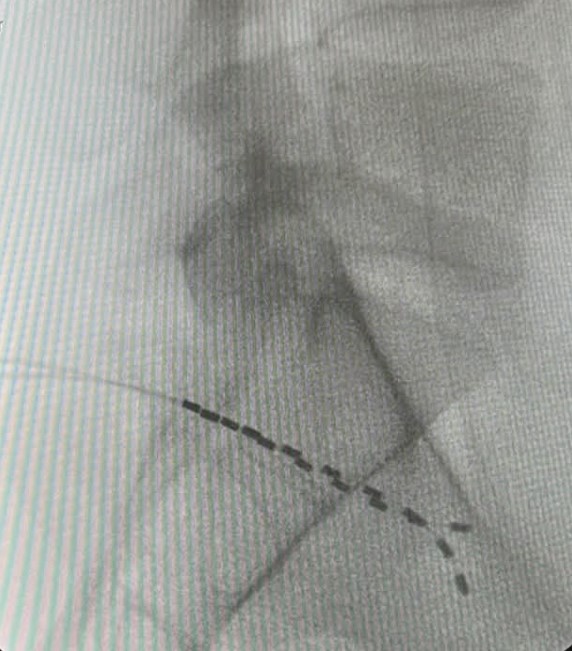

Η τεχνική της διέγερσης του DRG είναι σχεδόν πανομοιότυπη με τη τεχνική διέγερσης του νωτιαίου μυελού. Ωστόσο, στόχο της νευροδιέγερσης εδώ αποτελεί το συγκεκριμένο γάγγλιο και όχι ο νωτιαίος μυελός. Τα γάγγλια της ραχιαίας ρίζας βρίσκονται στα μεσοσπονδύλια τρήματα.

Η διέγερση του DRG αφορά στην εμφύτευση ηλεκτροδίου που στέλνει ηλεκτρικά ερεθίσματα στη συγκεκριμένη περιοχή. Οι ώσεις αυτές διακόπτουν τη μετάδοση των σημάτων πόνου από το περιφερικό προς το κεντρικό νευρικό νευρικό σύστημα. Με απλά λόγια, η διέγερση του γαγγλίου τροποποιεί την αντίληψη του πόνου. Πριν την τελική εμφύτευση του ή των ηλεκτροδίων και τη σύνδεση αυτών με τη γεννήτρια, προηγείται διάστημα δοκιμαστικής διέγερσης με φορητή, εξωτερική γεννήτρια.